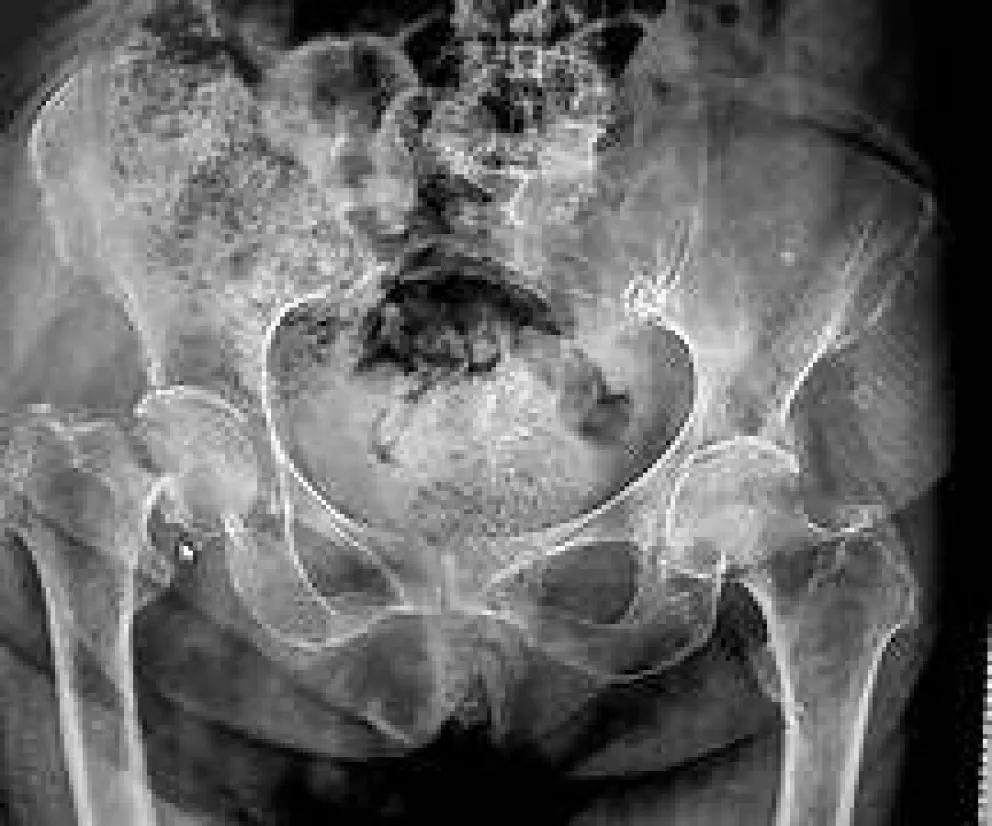

Una mujer de 62 años de General Roca sufrió una grave lesión mientras asistía al cumpleaños de su nieta en un salón de eventos. La caída, provocada por el piso mojado, le causó una fractura de cadera que derivó en una cirugía y un reemplazo total de la cadera izquierda. A raíz del hecho, la justicia condenó al establecimiento a pagar una indemnización por los perjuicios sufridos.

Una pericia médica determinó que padece una incapacidad parcial y permanente, mientras que una evaluación psicológica reveló ansiedad, angustia y un fuerte impacto en su autoestima.